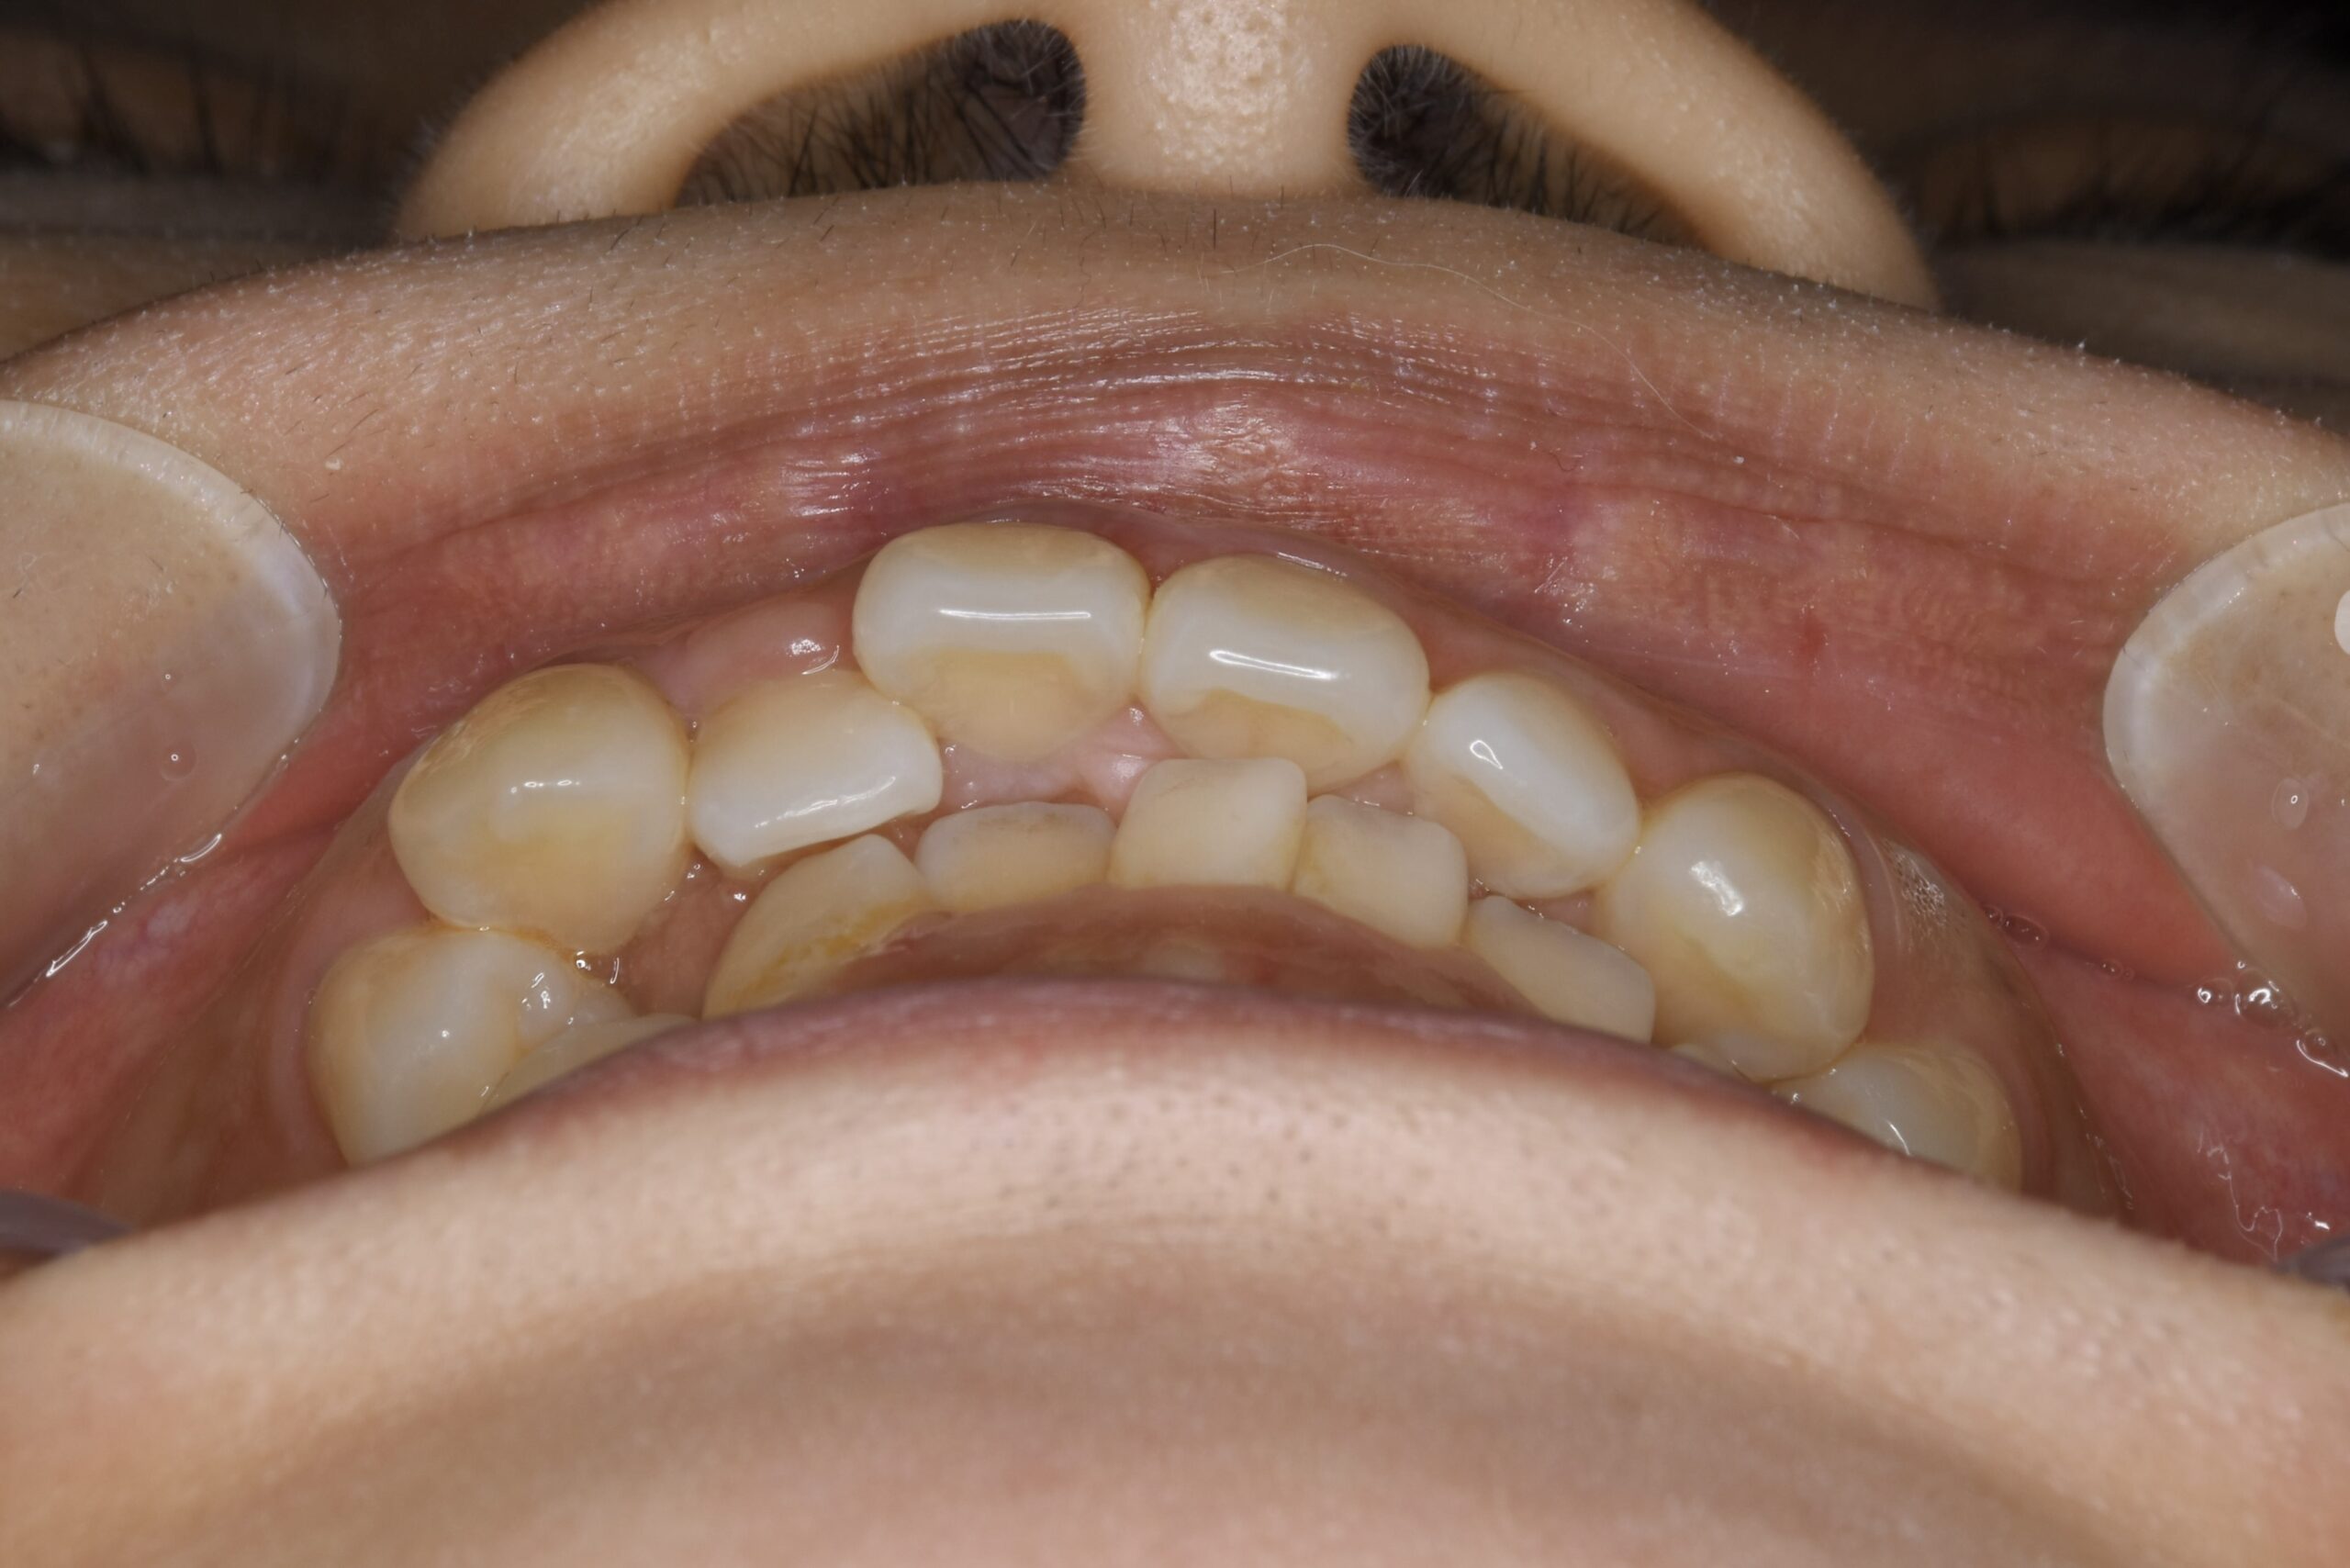

32歳 女性 治療期間:1年7ヶ月

BEFORE

主訴 口元が出ていて気になる。

診断名・主な症状 叢生を伴う上顎前突

治療内容 上下とも歯を2本抜いて、上の前歯を後方に引きながら、でこぼこを治しました。

使用装置 マウスピース矯正装置(インビザライン)

抜歯部位 上 両側4番目

下 右側4番目、左側5番目

治療期間 1年7ヶ月

通院回数 13回

費用 91万円程度(税別)   270

リスク・副作用 痛み、歯肉退縮、歯根吸収、抜歯に伴う出血や腫れが生じることがあります。